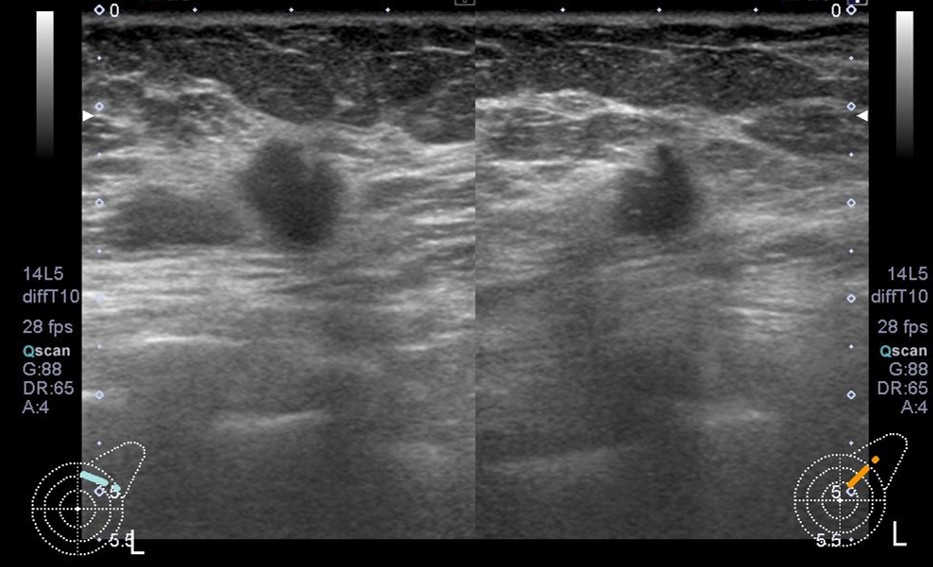

• 超音波

CD区域に楕円形・境界明瞭な低エコー腫瘤があり、背側に分葉状の突出部分がある。

線維腺腫の疑い

背側は乳管内病変も鑑別。増大があり、葉状腫瘍の可能性がある。

C区域に不整形・境界不明瞭な低エコー腫瘤がある。Haloを伴っている。

浸潤性乳管癌の疑い